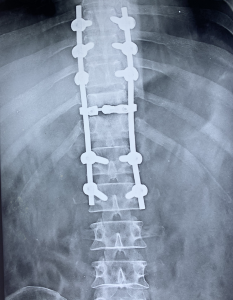

PROFILE TRAINING AND PRESENTATION Dr. Niranjanan Recieving Diploma SICOT degree in Rome, Italy Dr. Niranjanan being awarded fellowship certificate at Indian spinal injuries centre CLIINIC SOME OF Dr. NIRANJANAN's CASES